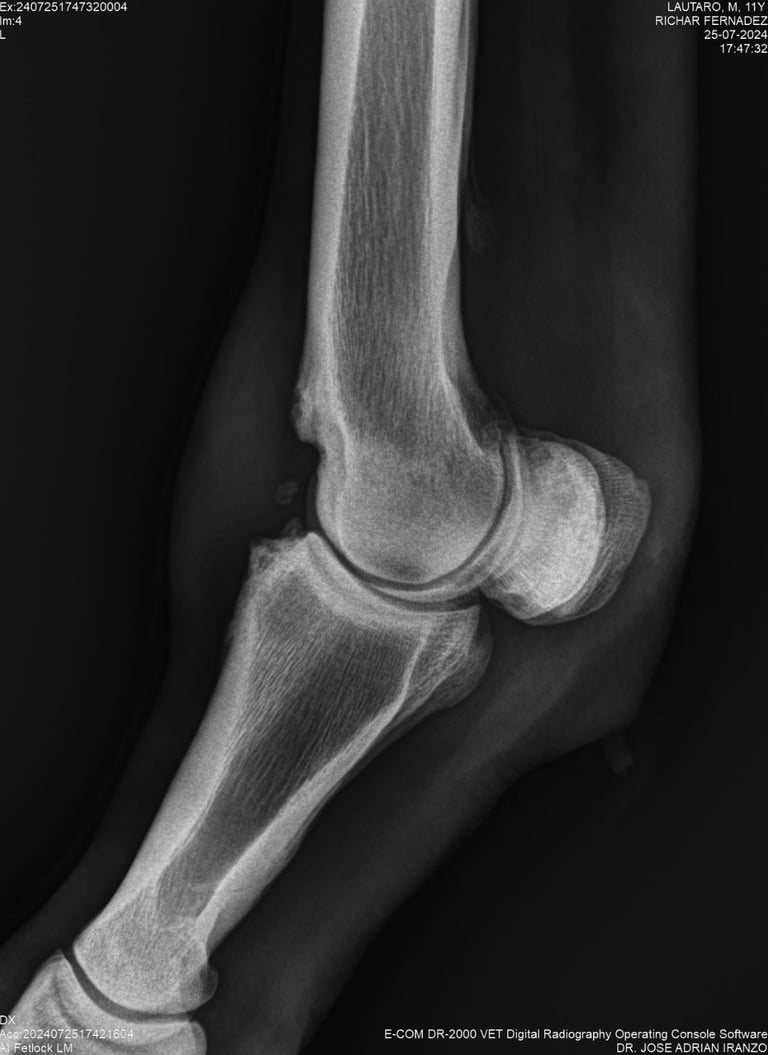

DIAGNOSTICO POR IMAGENES: ECOGRAFIA Y RADIOGRAFIA